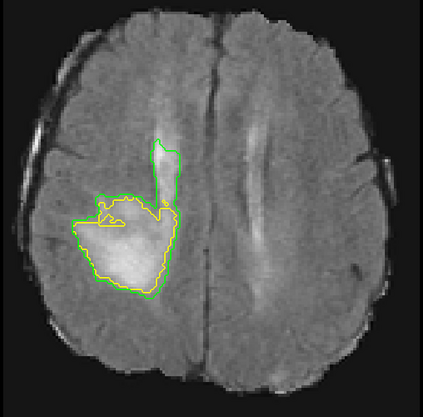

Despite the state-of-the-art performance for medical image segmentation, deep convolutional neural networks (CNNs) have rarely provided uncertainty estimations regarding their segmentation outputs, e.g., model (epistemic) and image-based (aleatoric) uncertainties. In this work, we analyze these different types of uncertainties for CNN-based 2D and 3D medical image segmentation tasks. We additionally propose a test-time augmentation-based aleatoric uncertainty to analyze the effect of different transformations of the input image on the segmentation output. Test-time augmentation has been previously used to improve segmentation accuracy, yet not been formulated in a consistent mathematical framework. Hence, we also propose a theoretical formulation of test-time augmentation, where a distribution of the prediction is estimated by Monte Carlo simulation with prior distributions of parameters in an image acquisition model that involves image transformations and noise. We compare and combine our proposed aleatoric uncertainty with model uncertainty. Experiments with segmentation of fetal brains and brain tumors from 2D and 3D Magnetic Resonance Images (MRI) showed that 1) the test-time augmentation-based aleatoric uncertainty provides a better uncertainty estimation than calculating the test-time dropout-based model uncertainty alone and helps to reduce overconfident incorrect predictions, and 2) our test-time augmentation outperforms a single-prediction baseline and dropout-based multiple predictions.